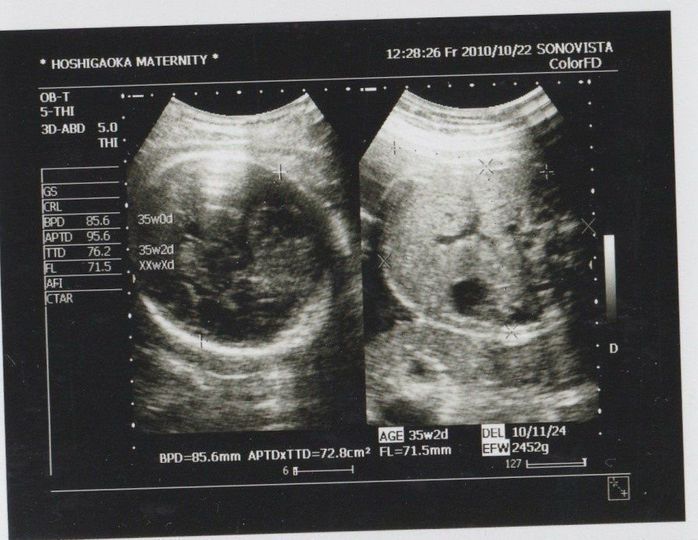

妊娠35週目のエコー写真

まだ正期産前ですが、推定体重から計算される出産予定日までもが、3週間近く早くなっていました。誤差はあるとは言え、順調なのは嬉しい半面、「大きくなりすぎて難産になるのでは」と不安な気持ちも隠しきれませんでした。